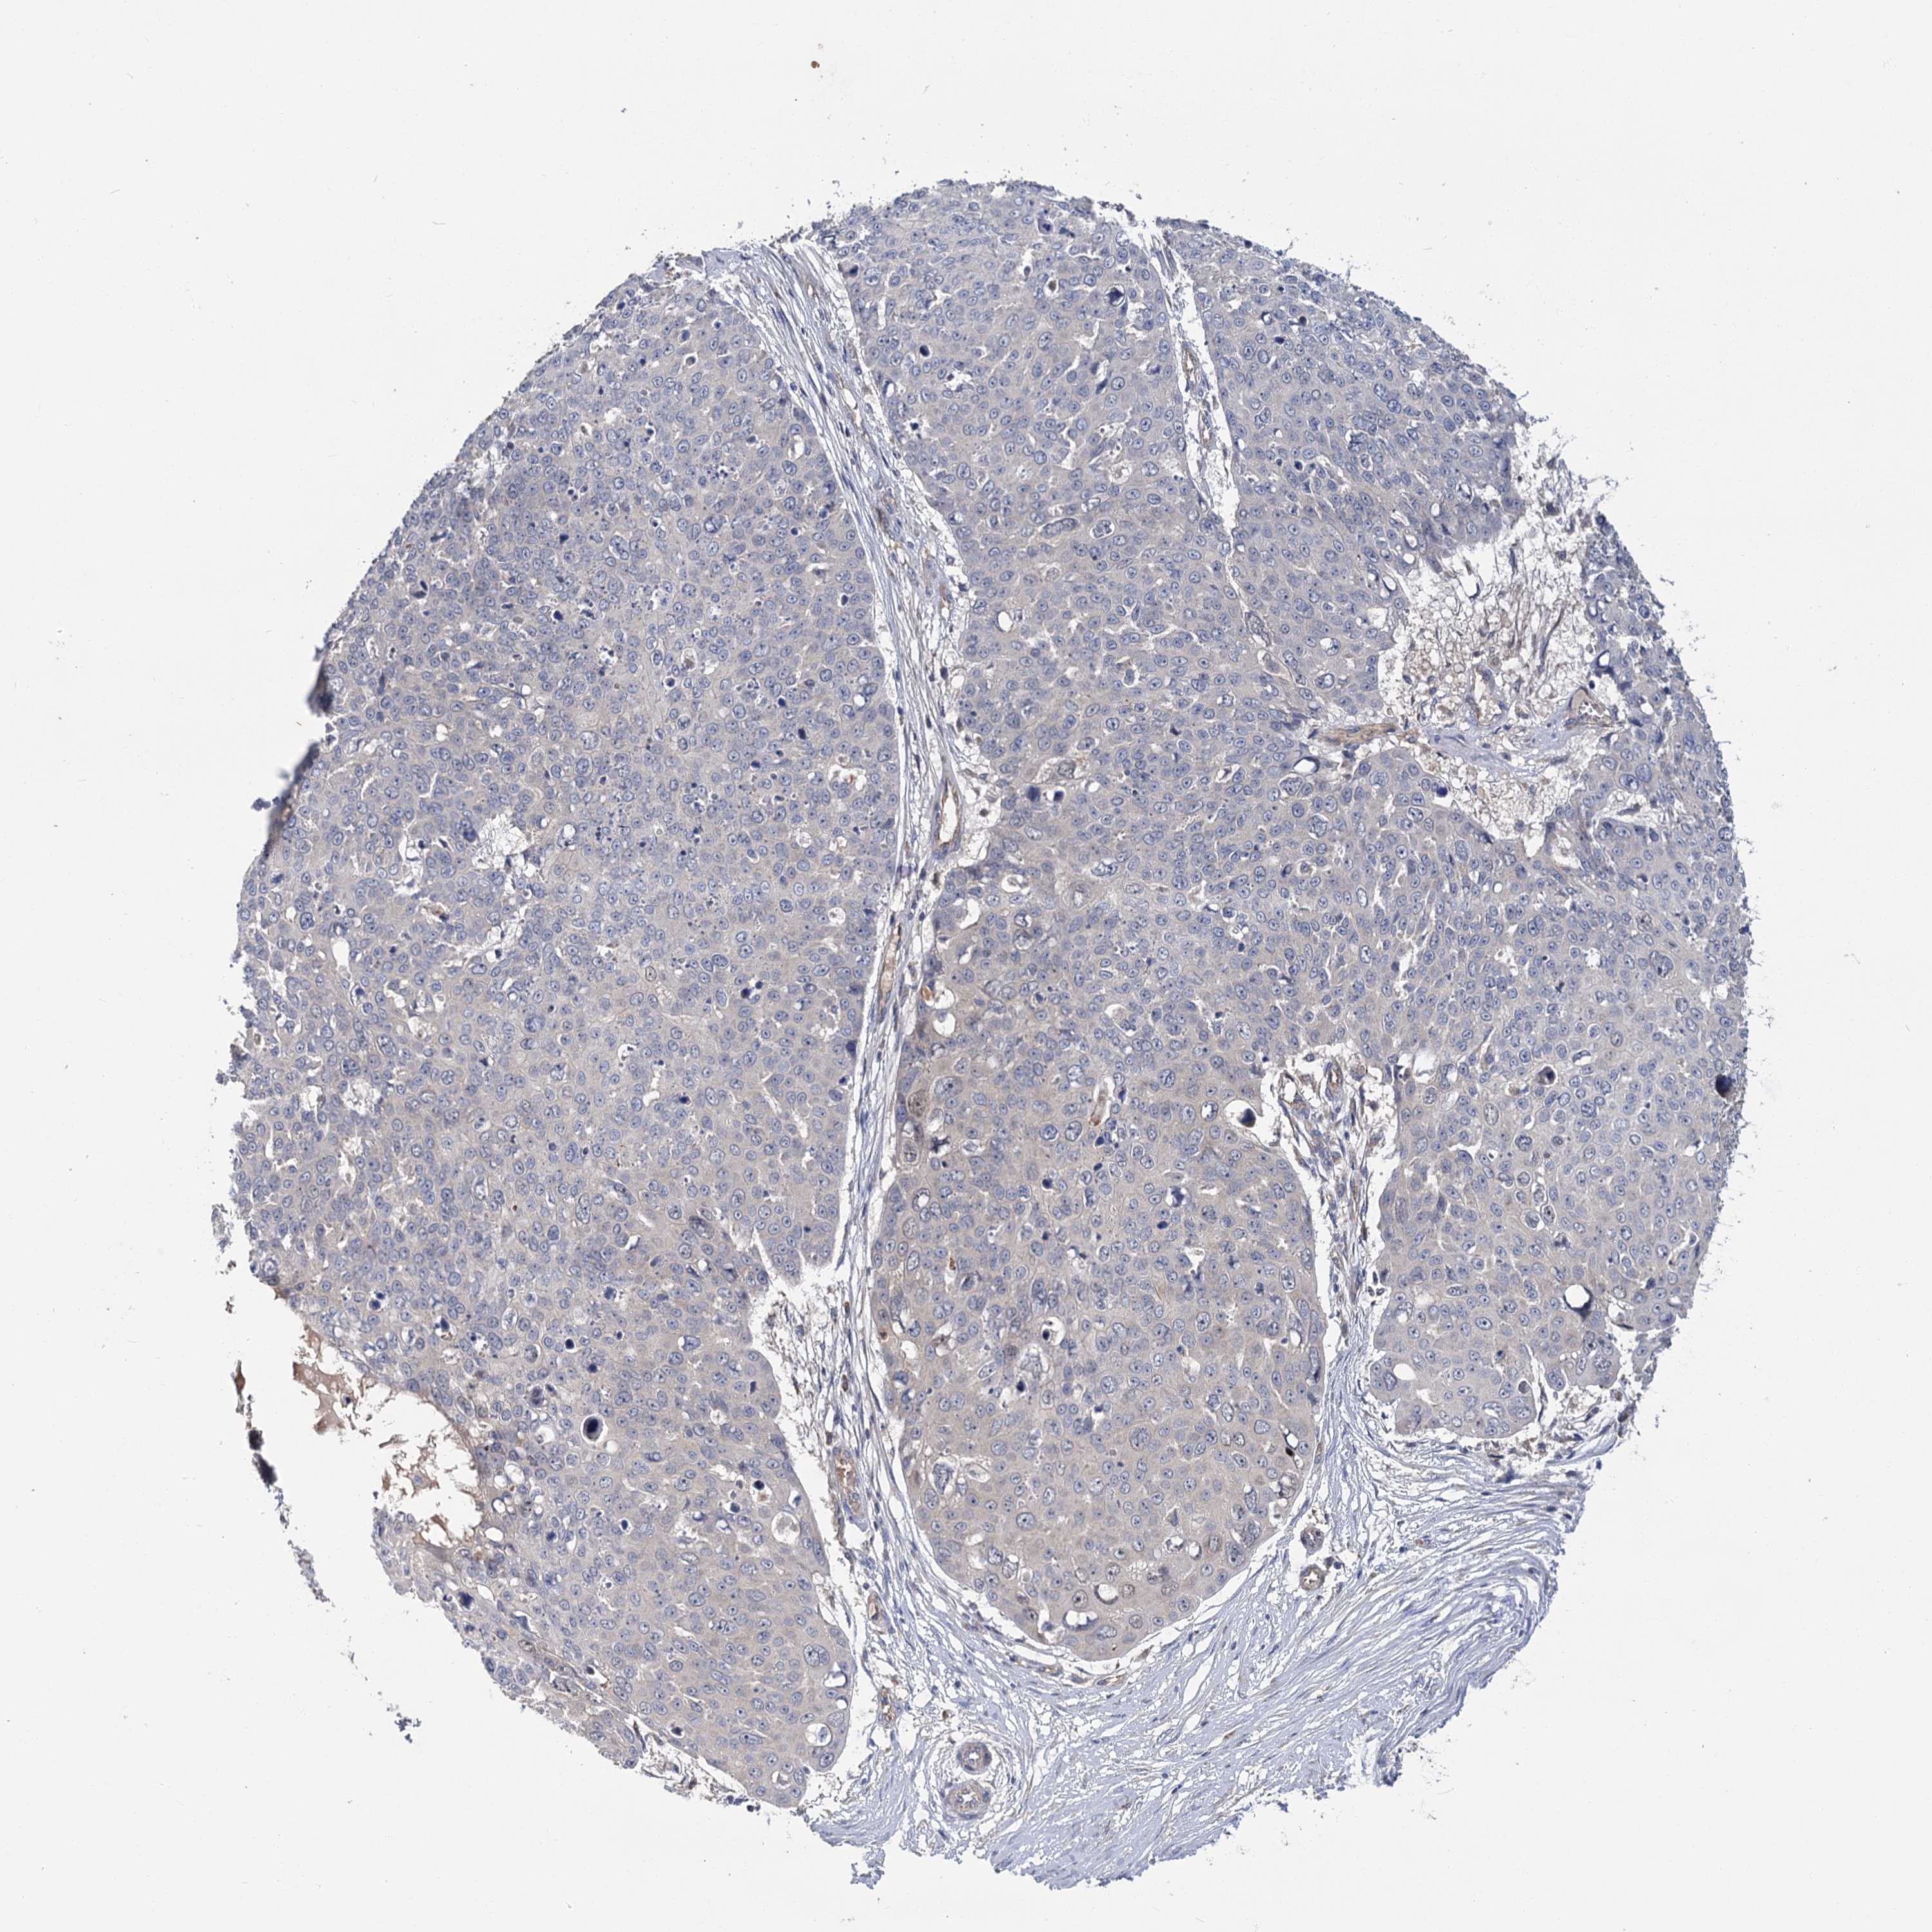

SKIN CANCER - Protein expressioni

A mouse-over function shows sample information and annotation data. Click on an image to view it in a full screen mode. Samples can be filtered based on level of antibody staining by selecting one or several of the following categories: high, medium, low and not detected. The assay and annotation is described here.

Each image is clickable and will lead to virtual microscopy that enables deeper exploration of all samples and also displays staining intensity scores, fraction scores and subcellular localization as well as patient and tissue information for each sample.

Antibody HPA039015

Basal cell carcinoma